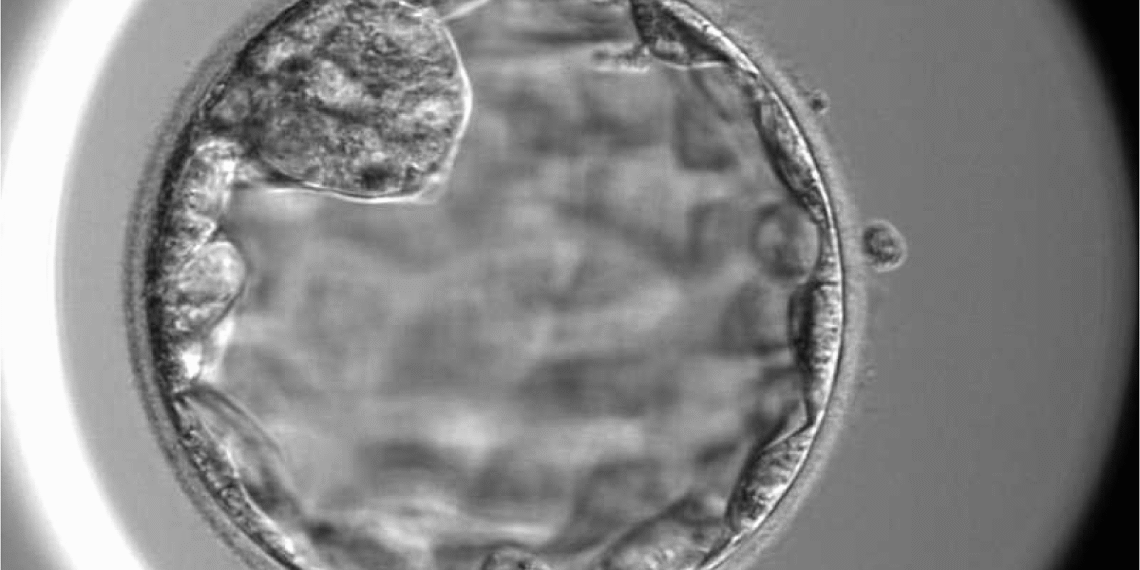

Bác sĩ Thủy kích thích buồng trứng cho bệnh nhân, thu 19 trứng, hầu hết có hình thái móp méo, bào tương rỗ, không phát triển đến giai đoạn trưởng thành. Chuyên viên phôi học nỗ lực lọc rửa, tiếp tục nuôi cấy toàn bộ trứng trong môi trường tối ưu và chọn lọc được 14 trứng đủ điều kiện để thụ tinh cùng tinh trùng của người chồng. Kết quả thu được 3 phôi ngày 3, tiếp tục nuôi lên giai đoạn ngày 5 thì hai phôi ngừng phát triển, còn phôi duy nhất vượt qua sàng lọc tự nhiên khắc nghiệt. Phần mềm trí tuệ nhân tạo (AI) chấm điểm chất lượng phôi loại 3, mức độ trung bình.

Hình ảnh phôi ngày 5 được nuôi cấy tại IVF Tâm Anh TP HCM. Ảnh: Thu Thảo